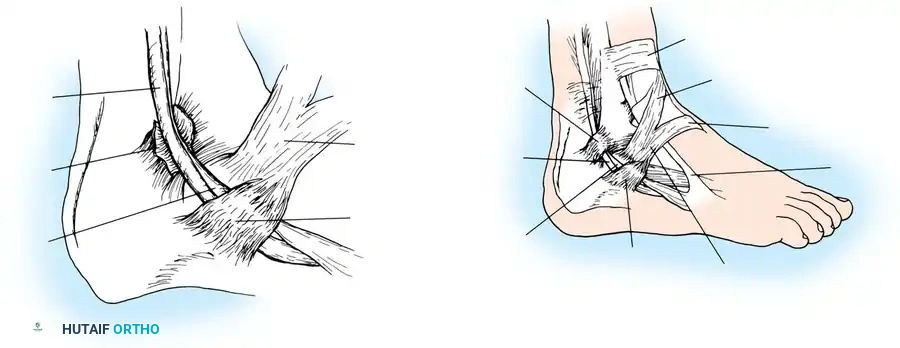

3. Retinaculum Release and Exploration

Open the sheath of the peroneal tendons proximally and trace the tendons distally to the superior peroneal retinaculum (SPR).

- If the tendons appear normal both proximal and distal to the SPR, incise only half of the retinaculum (about 1 cm or less) to preserve its stabilizing function.

- If the SPR is thickened or the sheath is fibrotic—suggesting impaired tendon excursion—incise the entire retinaculum and inspect the inferior peroneal retinaculum (IPR). In isolated tenosynovitis, it is unusual to require the release of both retinacula.

Carefully evaluate the septum that extends from the fibula to the SPR, separating the peroneus longus and brevis. An accessory peroneal tendon (peroneus quartus) may be present in a separate compartment, contributing to overcrowding and stenosis. Release this septum and inspect the peroneus brevis, looking for any accessory slips.

4. Tenosynovectomy and Tendon Debridement

Perform a complete tenosynovectomy, sharply debriding hypertrophic portions of the tendon sheath with a small rongeur or dissecting scissors. The findings at surgery represent a continuum: from clear fluid and relatively normal-appearing tendons, to small linear tears, to thickened, fibrotic sheaths encasing grayish, degenerative tendons.

Inspect the tendons meticulously for attritional, longitudinal fissuring. This pathology is most commonly located on the deep (anterior) surface of the peroneus brevis tendon, where it is compressed against the fibula by the overlying peroneus longus.

If the tear involves less than 50% of the tendon's cross-sectional area, excise the smaller, degenerative section of the tendon completely. The remaining viable portion is then tubularized to restore a smooth gliding surface. This is achieved using a running 3-0 absorbable, braided suture, burying the knots to minimize friction.

Perform a side-to-side tenodesis of the proximal and distal stumps of the peroneus brevis to the intact peroneus longus tendon.

* The proximal tenodesis should be performed well above the level of the SPR, approximately 3 to 4 cm proximal to the ankle joint, generally at the musculotendinous junction of the peroneus brevis.

* Complete the repair using 2-0 nonabsorbable, braided sutures (e.g., Ethibond or FiberWire), ensuring appropriate tension is maintained to preserve eversion strength.

Distally, leave the tendon sheaths for both the brevis and longus open to prevent postoperative stenosis. Suture the brevis and longus tendons together distally with 2-0 nonabsorbable sutures if a tenodesis was performed.

Repair the superior peroneal retinaculum over the tendons using 2-0 absorbable sutures, ensuring the tendons do not subluxate during passive dorsiflexion and eversion. Leave the remainder of the tendon sheath open. Close the subcutaneous tissues and skin in a standard layered fashion.